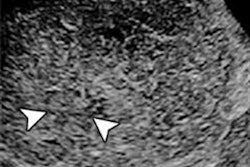

Karur and colleagues compared the sensitivity, specificity, and diagnostic accuracy of contrast-enhanced ultrasound with that of unenhanced ultrasound to characterize focal liver lesions. They also compared the enhancement characteristics of these lesions in various phases of contrast-enhanced ultrasound with contrast CT, and investigated the time to washout for malignant liver lesions.

Patients underwent contrast-enhanced ultrasound with a 1.2- to 2.5-mL dose of Bracco's Lumason ultrasound contrast agent (previously known as SonoVue in the U.S.), followed by a saline flush of 5 mL. The lesions were observed in three phases from time of injection for up to five minutes: arterial (25 to 35 seconds), extended portal venous (35 to 90 seconds), and delayed (90 seconds through the remaining observation time).